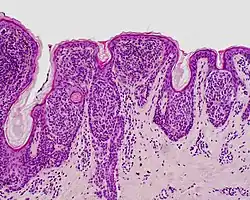

| Dysplastic nevus | Usually a compound nevus with cellular and architectural dysplasia. Like typical moles, dysplastic nevi can be flat or raised. While they vary in size, dysplastic nevi are typically larger than normal moles and tend to have irregular borders and irregular coloration. Hence, they resemble melanoma, appear worrisome, and are often removed to clarify the diagnosis. Dysplastic nevi are markers of risk when they are numerous, such as in people with dysplastic nevus syndrome. According to the National Institute of Health (NIH), doctors believe that, when part of a series or syndrome of multiple moles, dysplastic nevi are more likely than ordinary moles to develop into the most virulent type of skin cancer called melanoma.[19] | ![]() In this case, the central portion is a complex papule, and the periphery is macular, irregular, indistinct and slightly pink. |

Characteristic rete ridge bridging, shouldering, and lamellar fibrosis. H&E stain.